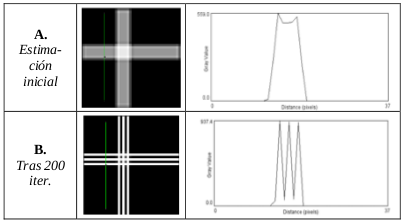

In this work, we propose a novel 4D reconstruction method for PET which is based on spatiotemporal total variation (ST-TV). The ST-TV method takes advantage of image redundancies in 4D and was efficiently implemented using the split Bregman formulation, which has been shown to be optimal for decreasing noise while maintaining image quality. To evaluate the proposed approach we simulated data for a dynamic numerical phantom with different number of counts to mimic high and low Signal-to-Noise Ratio (SNR) scenarios.

| JOURNAL | IEEE Nuclear Science Symposium & Medical Imaging Conference, 2014 |

| ABSTRACT | Dynamic PET images suffer from low signaltonoise ratio (SNR), especially for fast contrast uptake measurements due to the small number of counts available in those time frames. In this work, we propose a 4D reconstruction method based on spatiotemporal total variation (STTV) which takes advantage of image redundancies in 4D. The 4D STTV method was efficiently implemented using the Split Bregman formulation, which has been shown to be optimal for decreasing noise while maintaining image quality. To evaluate the proposed approach we acquired listmode data from a NEMA image quality phantom in a preclinical PET/CT scanner. |